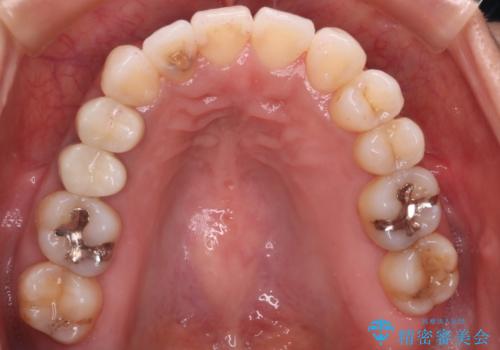

【審美装置】抜歯の本数最小限で行った矯正治療

- 審美装置

- 全体のがたつきを主訴に来院されました。4番目の歯を4本抜歯も検討しましたが、口元が下がりすぎてしまうリスクと2番目の転位うが著しく並べるのにかかる期間を考慮し、変則的な抜歯をし、並べる計画を立てました。

抜歯矯正のため2年はかかってしまいましたが、きれいに並び患者様にも満足頂きました。